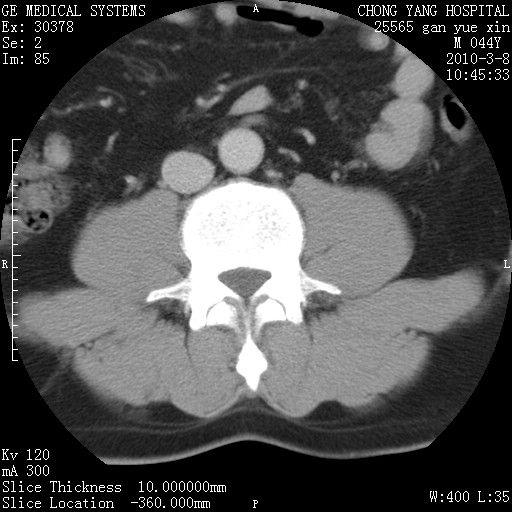

标题: CT24940:主动脉增强,典型病例。 [打印本页]

标题: CT24940:主动脉增强,典型病例。

夹层动脉瘤。

动脉夹层

夹层动脉瘤,典型

主动脉夹层。

动脉夹层的分型:

⒈debakey分型:根据主动脉夹层累及部位,分为三型:ⅰ型:原发破口位于升主动脉或主动脉弓部,夹层累及升主动脉、主动脉弓部、胸主动脉、腹主动脉大部或全部,少数可累及髂动脉。ⅱ型:原发破口位于升主动脉,夹层累及升主动脉,少数可累及部分主动脉弓。ⅲ型:原发破口位于左锁骨下动脉开口远端,根据夹层累及范围又分为ⅲa,ⅲb。ⅲa型:夹层累及胸主动脉。ⅲb型:夹层累及升主动脉、腹主动脉大部或全部。少数可累及髂动脉。

⒉stanford分型:a型:夹层累及升主动脉,无论远端范围如何。b型:夹层累及左锁骨下动脉开口以远的降主动脉。

夹层动脉瘤,少量胸水

夹层动脉瘤;左侧少量胸腔积液。

典型主动脉夹层。